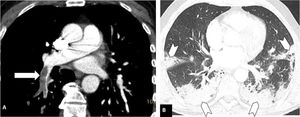

Depending on the location of the most proximal filling defect, thromboembolic involvement was classified as: a) proximal, if the most proximal thrombus was located in the trunk of the pulmonary artery or in the main pulmonary arteries (Fig. 1); b) medial, if the material was located in the proximal lobar or segmental arteries (Fig. 2); or c) distal, if the involvement was distal segmental or subsegmental (Fig. 3).17

Pulmonary thromboembolism in a medial location in a patient with moderate parenchymal involvement by COVID-19. Chest CT angiography. A) Filling defect in the right lower lobar artery (white arrow). B) Parenchymal involvement with peripheral consolidations in the posterior region of both lower lobes, the medial lobe and the lingula (arrow heads), involving 30-60% of the lung parenchyma.

Severity of involvement was classified according to extent of lesions in the lung parenchyma as: a) normal: no involvement; b) mild: <30% involvement of the lung parenchyma (Fig. 3); c) moderate: 30–60% involvement (Fig. 2); or d) severe: >60% involvement of the lung parenchyma (Fig. 1).20–24